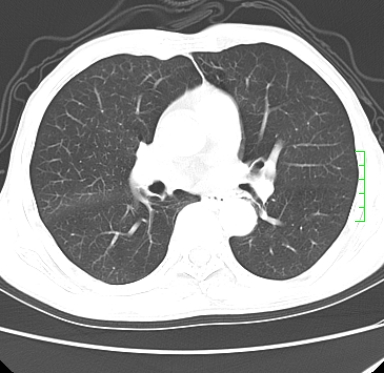

m,73y。膝关节疼痛伴双下肢水肿。入院常规胸片发现结节灶。增强为静脉期。

浅分叶、棘突,考虑右下肺周围型肺癌

考虑周围型肺癌  ,双上肺结核。

肿块周围可见局限性气肿,考虑肺癌可能性大。双肺上叶继发型肺结核。

指套征,强化明显,近侧肺组织局限性肺气肿,考虑支气管类癌,慢支、肺气肿、双上陈旧性tb、冠脉钙化。

鉴别:先天性支气管闭锁,变态反应性支气管肺曲霉菌病,肺癌,支气管囊肿,支扩黏液嵌塞。

1)考虑右肺下叶周围型肺癌。2)右肺上叶及左肺感染性病变(结核可能)。3)肺气肿。4)冠状动脉钙化。